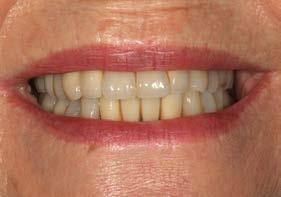

Seguimiento clínico a 25 años de una rehabilitación implantosoportada

Se presenta el caso de una paciente de sexo femenino, de 55 años, que acude a consulta portando una prótesis removible superior anclada a un molar remanente correspondiente a la pieza 17, la cual presenta una marcada pérdida ósea. El resto de las piezas dentales habían sido previamente extraídas debido a enfermedad periodontal. La paciente solicita una alternativa a su prótesis actual, ya que no satisface sus necesidades estéticas ni funcionales.

La paciente continúa bajo seguimiento periodontal. A los 5 años se observa estabilidad clínica del tratamiento (Figuras 22–24), sin recesiones gingivales ni pérdida ósea asociada en las imágenes clínicas y radiográficas.

Un año más tarde, al finalizar el periodo de seguimiento (24 años), las fotografías intraorales evidenciaron ligeras alteraciones de los tejidos blandos, con pequeñas troneras abiertas,

más evidentes en los dientes naturales conservados que en las restauraciones implantosoportadas. A pesar de estos cambios, el resultado global se consideró satisfactorio desde el punto de vista funcional y estético, especialmente en comparación con la situación clínica y radiográfica inicial previa al tratamiento (Figuras 26–31).